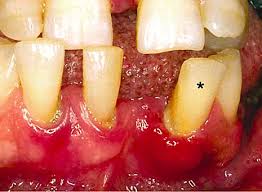

Often neglected by patients with diabetes, oral health is an important indication of poorly managed blood sugar. According to Diabetesmonitor.com, people with diabetes are 2 to 3 times more likely than person without diabetes to have destructive periodontal disease such as periodontitis. Also, uncontrolled diabetes can decrease saliva flow which can cause drying of mouth that may lead to infections, sores, or even ulcers and tooth decay. For people with diabetes who smokes, there is a high chance of oral thrush and periodontal disease. Smoking also decrease or impair blood flow to the gums which will greatly affect wound healing.